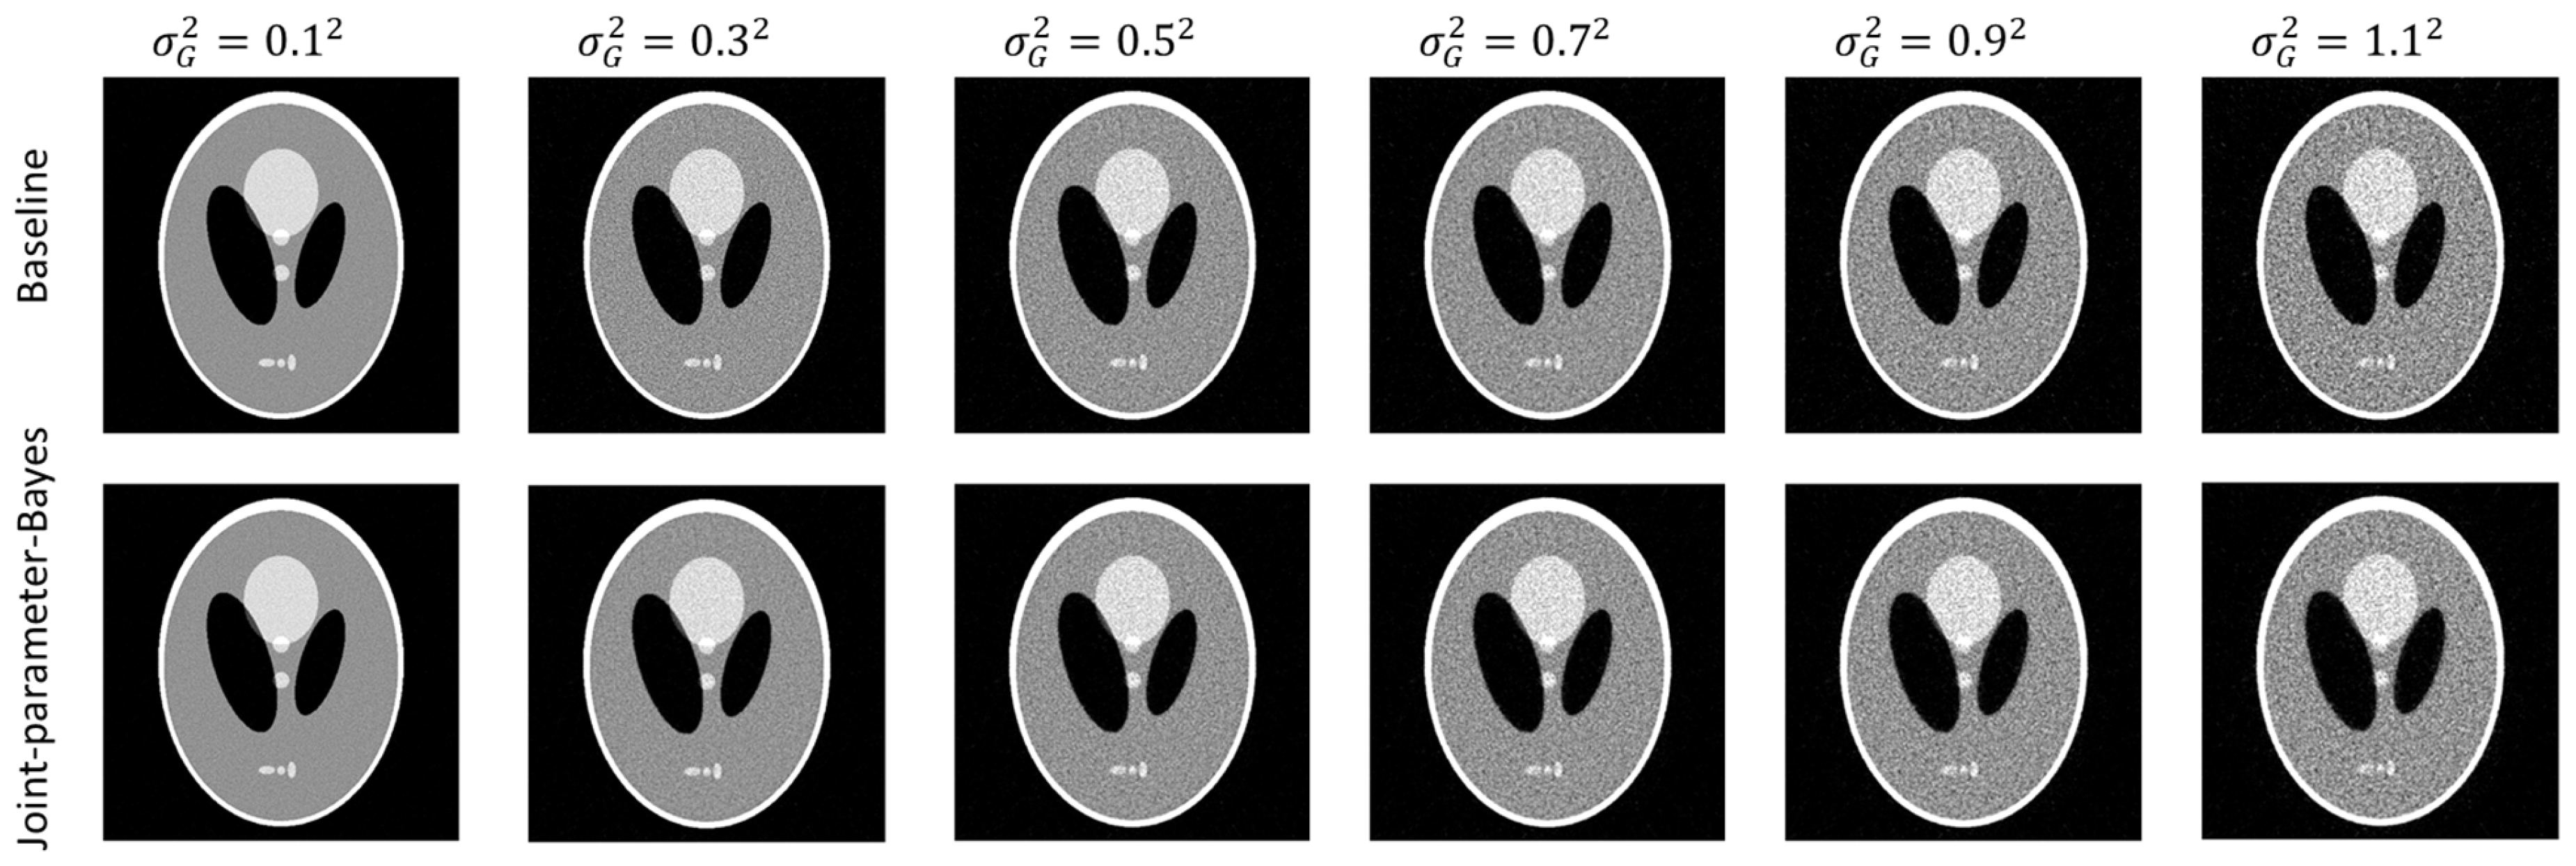

Figure 2 shows the reconstructed images both by the conventional MAP (baseline) and joint-parameter-Bayes with different noise levels. It can be observed that the results are comparable. The quantitative comparisons are summarized in Table 1 which are also consistent with our visual inspection. However, their computation time is quite different based on the iterations they use in Table 1. The proposed joint-parameter-Bayes saves approximately 66~88% of computation time in comparison with the baseline method. The number of iterations for joint-parameter-Bayes is further discussed in the stopping criterion subsection. To test the robustness, we performed the experiments on two other noise types: (1) Poisson-like signal-dependent noise to post-log sinogram data; (2) Poisson noise to the pre-log transmission data. We repeated the above evaluations and yielded very similar results, which can be found in the Appendix A. Some details of the two noise models are also be discussed in the following subsections.

Figure 2.

Comparison of reconstructed images between the conventional MAP (top row) and joint-parameter-Bayes (bottom row). The display window is [0, 0.035] mm−1.

Figure A1 and Table A1 present the comparison results between the baseline and the proposed joint-parameter-Bayes on Poisson noise in post-log sinogram data. Figure A2 and Table A2 present the comparison results between the baseline and the proposed joint-parameter-Bayes on Poisson noise to pre-log transmission data.

Figure A1.

Comparison of reconstructed images between the conventional MAP (baseline) and joint-parameter-Bayes with Poisson noise to post-log sinogram data.